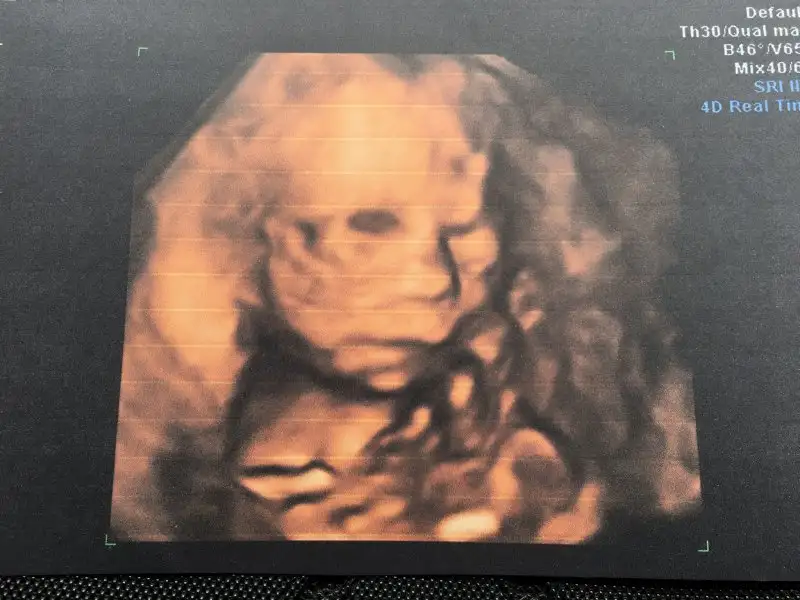

Pitircik yerim seni...Eki Görüntüle 2055849 Eki Görüntüle 2055850 Günaydın canlar bakın kızıma

28,5 cm 560 gr olmuş kızım :) Plasenta azcık yana kaymış biraz daha kayarsa kurtaracak ama şuan hala bebeği alacağımız yerde olduğu için kanama riski var dinlenmene devam et tamam mı dedi